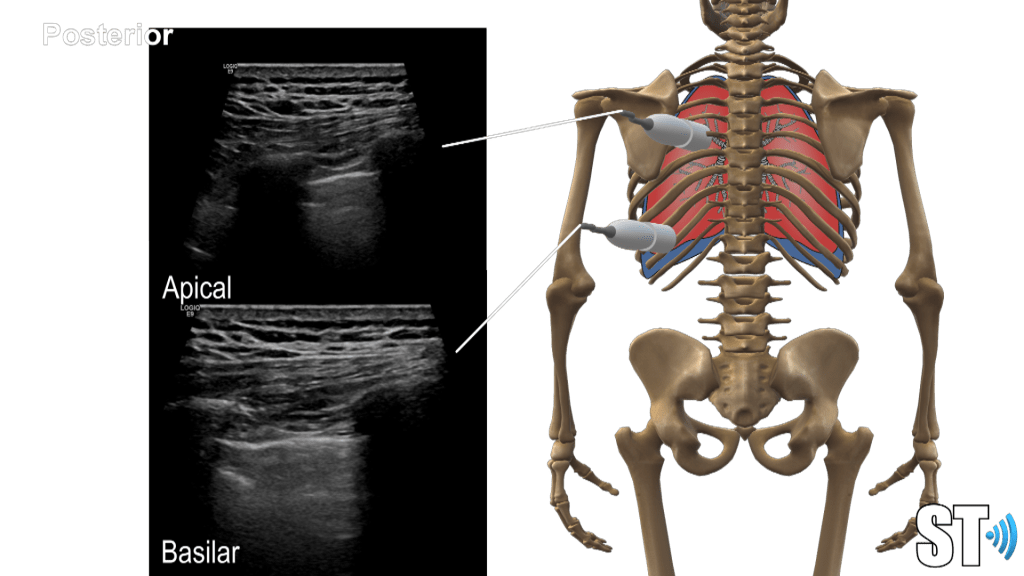

Using a linear, sector or small curvilnear transducer, divide the chest into parasternal, anterior and posterior axillary lines. Scan the basilar, mid and apical or upper portions of the chest. Scan the posterior aspect of the chest also at the base, mid and superior portions.

Anterior

Axillary

Posterior

You may scan the patient in supine, upright and prone positions (if intubated supine may be the only available scan approach).